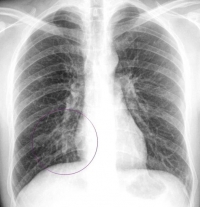

Этот вид пневмонии характеризуется поражением одной доли лёгкого, целого лёгкого или даже обоих лёгких. Чем больше объём поражения — тем тяжелее протекает процесс. Вызывается крупозная пневмония пневмококком. Кроме повреждения ткани легкого бактерия, выделяя токсичные для человека вещества, действует на весь организм – сильно повышается температура, появляется озноб.